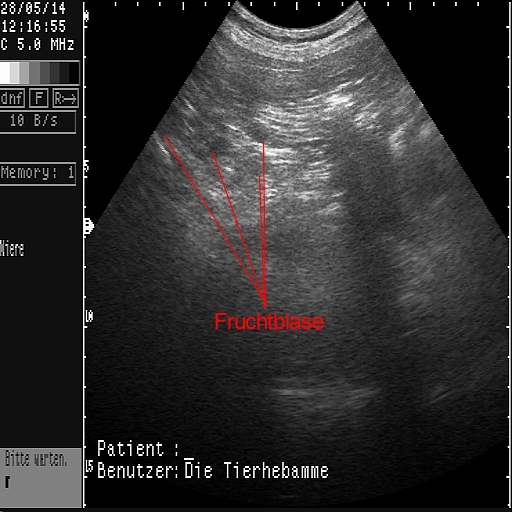

Das sind die ersten Ultraschallbilder vom 28.05.2014!

Es hat wirklich geklappt!

Die Tier-Hebamme hat 9 kleine Fruchtblasen gezählt...!!!

Wir haben die lange Wartezeit kaum ausgehalten und dann doch irgendwie geschafft! Mit einem positiven Ergenis, wie man an den Bildern sehen kann. Sage und schreibe neun kleine Fruchtblasen waren für das (geübte) Auge der Hebamme zu erkennen - wir haben nix gesehen....  Uns dafür aber unglaublich gefreut!!!!